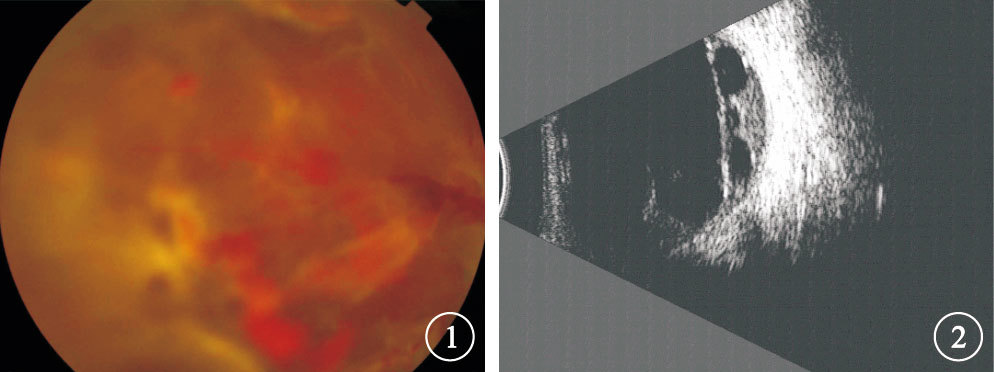

灌注液填充的38只眼中,一次手術后視網膜復位(圖 3,4)34只眼,占89.5%;手術后3個月內出現視網膜再脫離或視網膜未復位4只眼,占10.5%。視網膜再脫離或未復位4只眼中,視網膜再脫離為TRD 1只眼; 視網膜未復位,發現視網膜裂孔3只眼。 再次行玻璃體切割手術3只眼中,行15%C3F8、18%C2F6填充各1只眼;硅油填充1只眼,再次手術后3個月取出硅油。行2次玻璃體切割手術1只眼,第2次玻璃體切割手術行18%C2F6填充。隨訪期結束時所有患眼視網膜復位,最終視網膜復位率為100.0%。

灌注液填充的38只眼中,一次手術后視網膜復位(圖 3,4)34只眼,占89.5%;手術后3個月內出現視網膜再脫離或視網膜未復位4只眼,占10.5%。視網膜再脫離或未復位4只眼中,視網膜再脫離為TRD 1只眼; 視網膜未復位,發現視網膜裂孔3只眼。 再次行玻璃體切割手術3只眼中,行15%C3F8、18%C2F6填充各1只眼;硅油填充1只眼,再次手術后3個月取出硅油。行2次玻璃體切割手術1只眼,第2次玻璃體切割手術行18%C2F6填充。隨訪期結束時所有患眼視網膜復位,最終視網膜復位率為100.0%。